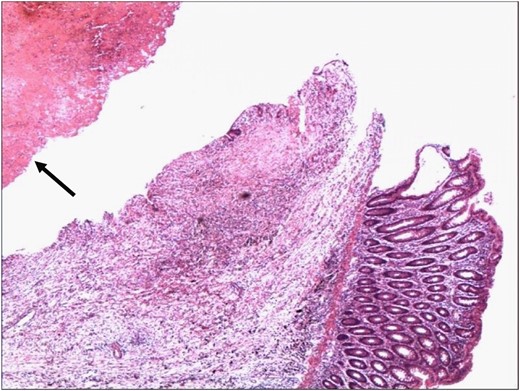

Histopathology confirmed the specimen to a SAA, with a 1 cm rupture through the colonic wall (Fig. 3A and B). On microscopic examination, the wall of the colon showed attenuation and loss of the muscle layers with bleeding into the lumen of the colon (Figs 4 and 5).

Point of rupture of the aneurysm into the lumen of the colon. The lumen of the aneurysm contains blood clot (arrowhead) (H&E 4×).